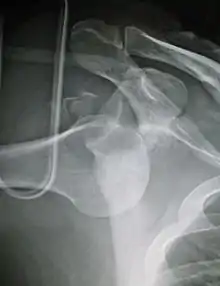

جراحة المنظار تطورت من إصلاح بانكارت واثبتت عدم الاستقرار الأمامي من الكتف. ومع ذلك، ثبت أن معدل الفشل بعد إصلاح بانكارت زيادة ملحوظة في المرضى الذين يعانون من فقدان العظام كبيرة من جلينويد في مثل هذه الحالات أبلغ عن نتائج محسنة مع بعض أشكال تعزيز العظام من جلينويد مثل عملية لاتارجيت.

على الرغم من أن الخلع الخلفى للكتف أقل شيوعاً بكثير، عدم ثبات المفصل لايتغير، ومرة أخرى قد يكون شكلاً من أشكال التعزيز العظام المطلوبة لمكافحة عدم الاستقرار.

لا تزال تلك الحالات التي تتسم بعدم الاستقراأخفقت في الاستجابة لإعادة التأهيل، والتي تقع تحت تصنيف أمبري وأشار سابقا إلى هناك. وهذا يحدث عادة بسبب كبسولة يفوق طاقتها وزائدة عن الحاجة التي لم يعد يوفر الاستقرار أو الدعم. تقليديا هذا قد استجابت أيضا إلى إجراء 'ريفينج' المعروفة باسم التحول الحافظة أقل شأنا أكثر مؤخرا، قد نفذ هذا الإجراء المنظار الداخلي، بدلاً من الجراحة المفتوحة، مرة أخرى مع النتائج قابلة للمقارنة ومؤخرا، الإجراء قد نفذ باستخدام تكنولوجيا الترددات الراديوية لتقليص كبسولة الكتف زائدة عن الحاجة، على الرغم من أن النتائج طويلة الأجل لهذا التطور غير مثبتة حاليا.